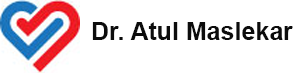

Right Atrial Lesion Pathways